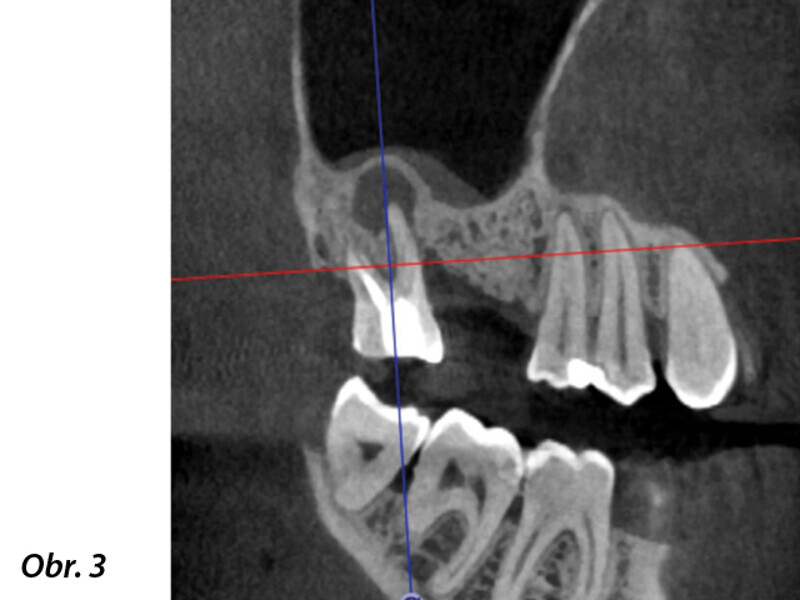

3D technologie v diagnostice a léčbě endodontických onemocnění